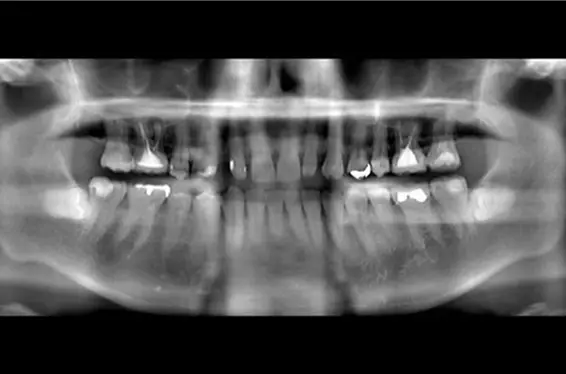

インプラントbefore after画像

• 費用:67万円

• 治療期間:8か月

• 治療内容:右上1、左上、歯根の破折により抜歯。大幅に骨か吸収していたために、1回目骨造成(こつぞうせい)(GBR)手術。4か月後、インプラント埋入手術。右上1番を支台とした、右上1にインプラント埋入,右上1支台,右上1,2のジルコニアインプラントブリッジ

リスクと副作用

• ・治療後、痛みや違和感、出血、腫れ、麻痺などが出る事があります。

• ・強い衝撃を与えると、被せ物が欠けたり割れたり、外れたりする事があります。

• ・メンテナンスが不十分な場合、インプラント周囲炎になる事があります。

• ・必ずしもご希望通りの見た目にならない事があります。